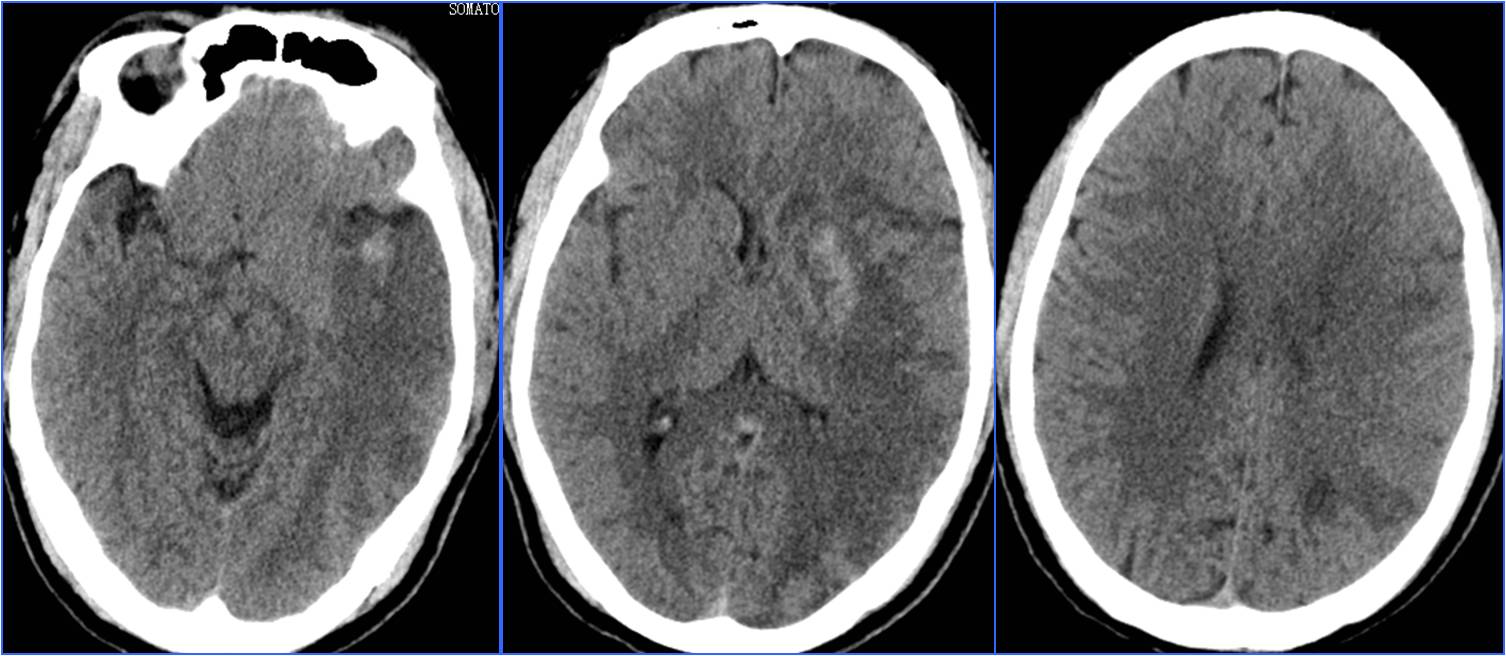

Case5 术后过度灌注、出血转化

》47岁,男,既往吸烟史20年

》12:00末次正常,15:00被发现言语不清、右侧肢体无力

》18:30到达急诊科,NIHSS 14分

》18:39完成头CT检查,19:28头MRA检查

》19:50行股动脉穿刺

》21:48结束手术

》术后24h NIHSS 8分

▼术前CT

▼术前MRA

▼术中给予替罗非班

▼术后24h头CT

▼术后72h 病情恶化,脑疝形成

▼去骨瓣减压,死亡